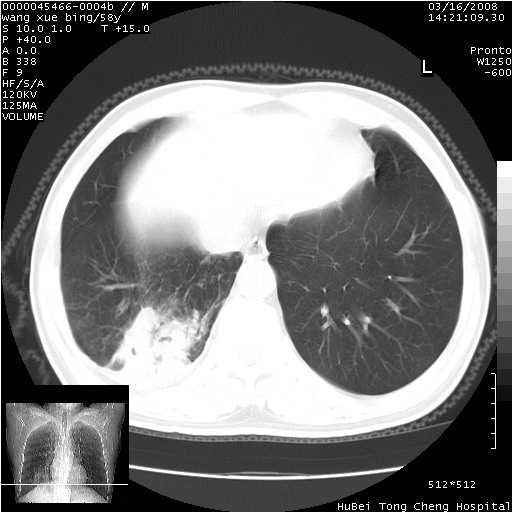

患者 男,58岁。咳嗽、咯血3月余。

胸部cr x线片提示:1)右下肺脓肿。2)右下肺周围型肺癌不排除。建议:行ct扫描检查。

胸部ct轴位平扫(层厚10mm,螺距1.5,重建间隔10mm),图像如下:

右肺下叶团块及不规则空洞,内壁不规则,外缘见粗长毛刺,临近胸膜明显增厚并与病灶关系密切。支持考虑:右肺肺脓肿!建议穿刺病理检查待除外周围型肺癌!

考虑右下肺中心型肺癌并远端阻塞性炎症及胸膜及纵隔淋巴转移

支持癌性空洞并远端阻塞性炎症